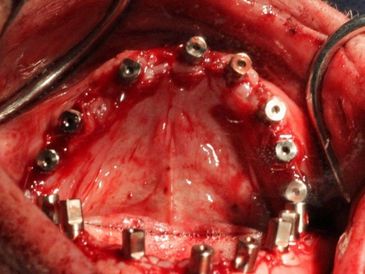

After CT scans are reviewed and implant locations are planned, Dr. Gibney begins implant surgery.

8 implants are surgically placed. Dr. Gibney takes impressions of the bottom implants with posts screwed in.

The second part of surgery begins on the upper arch.

The other dentists watch and discuss techniques with Dr. Gibney.

Gerald's dentist assists in the implant surgery.

Surgery on the lower arch is complete.